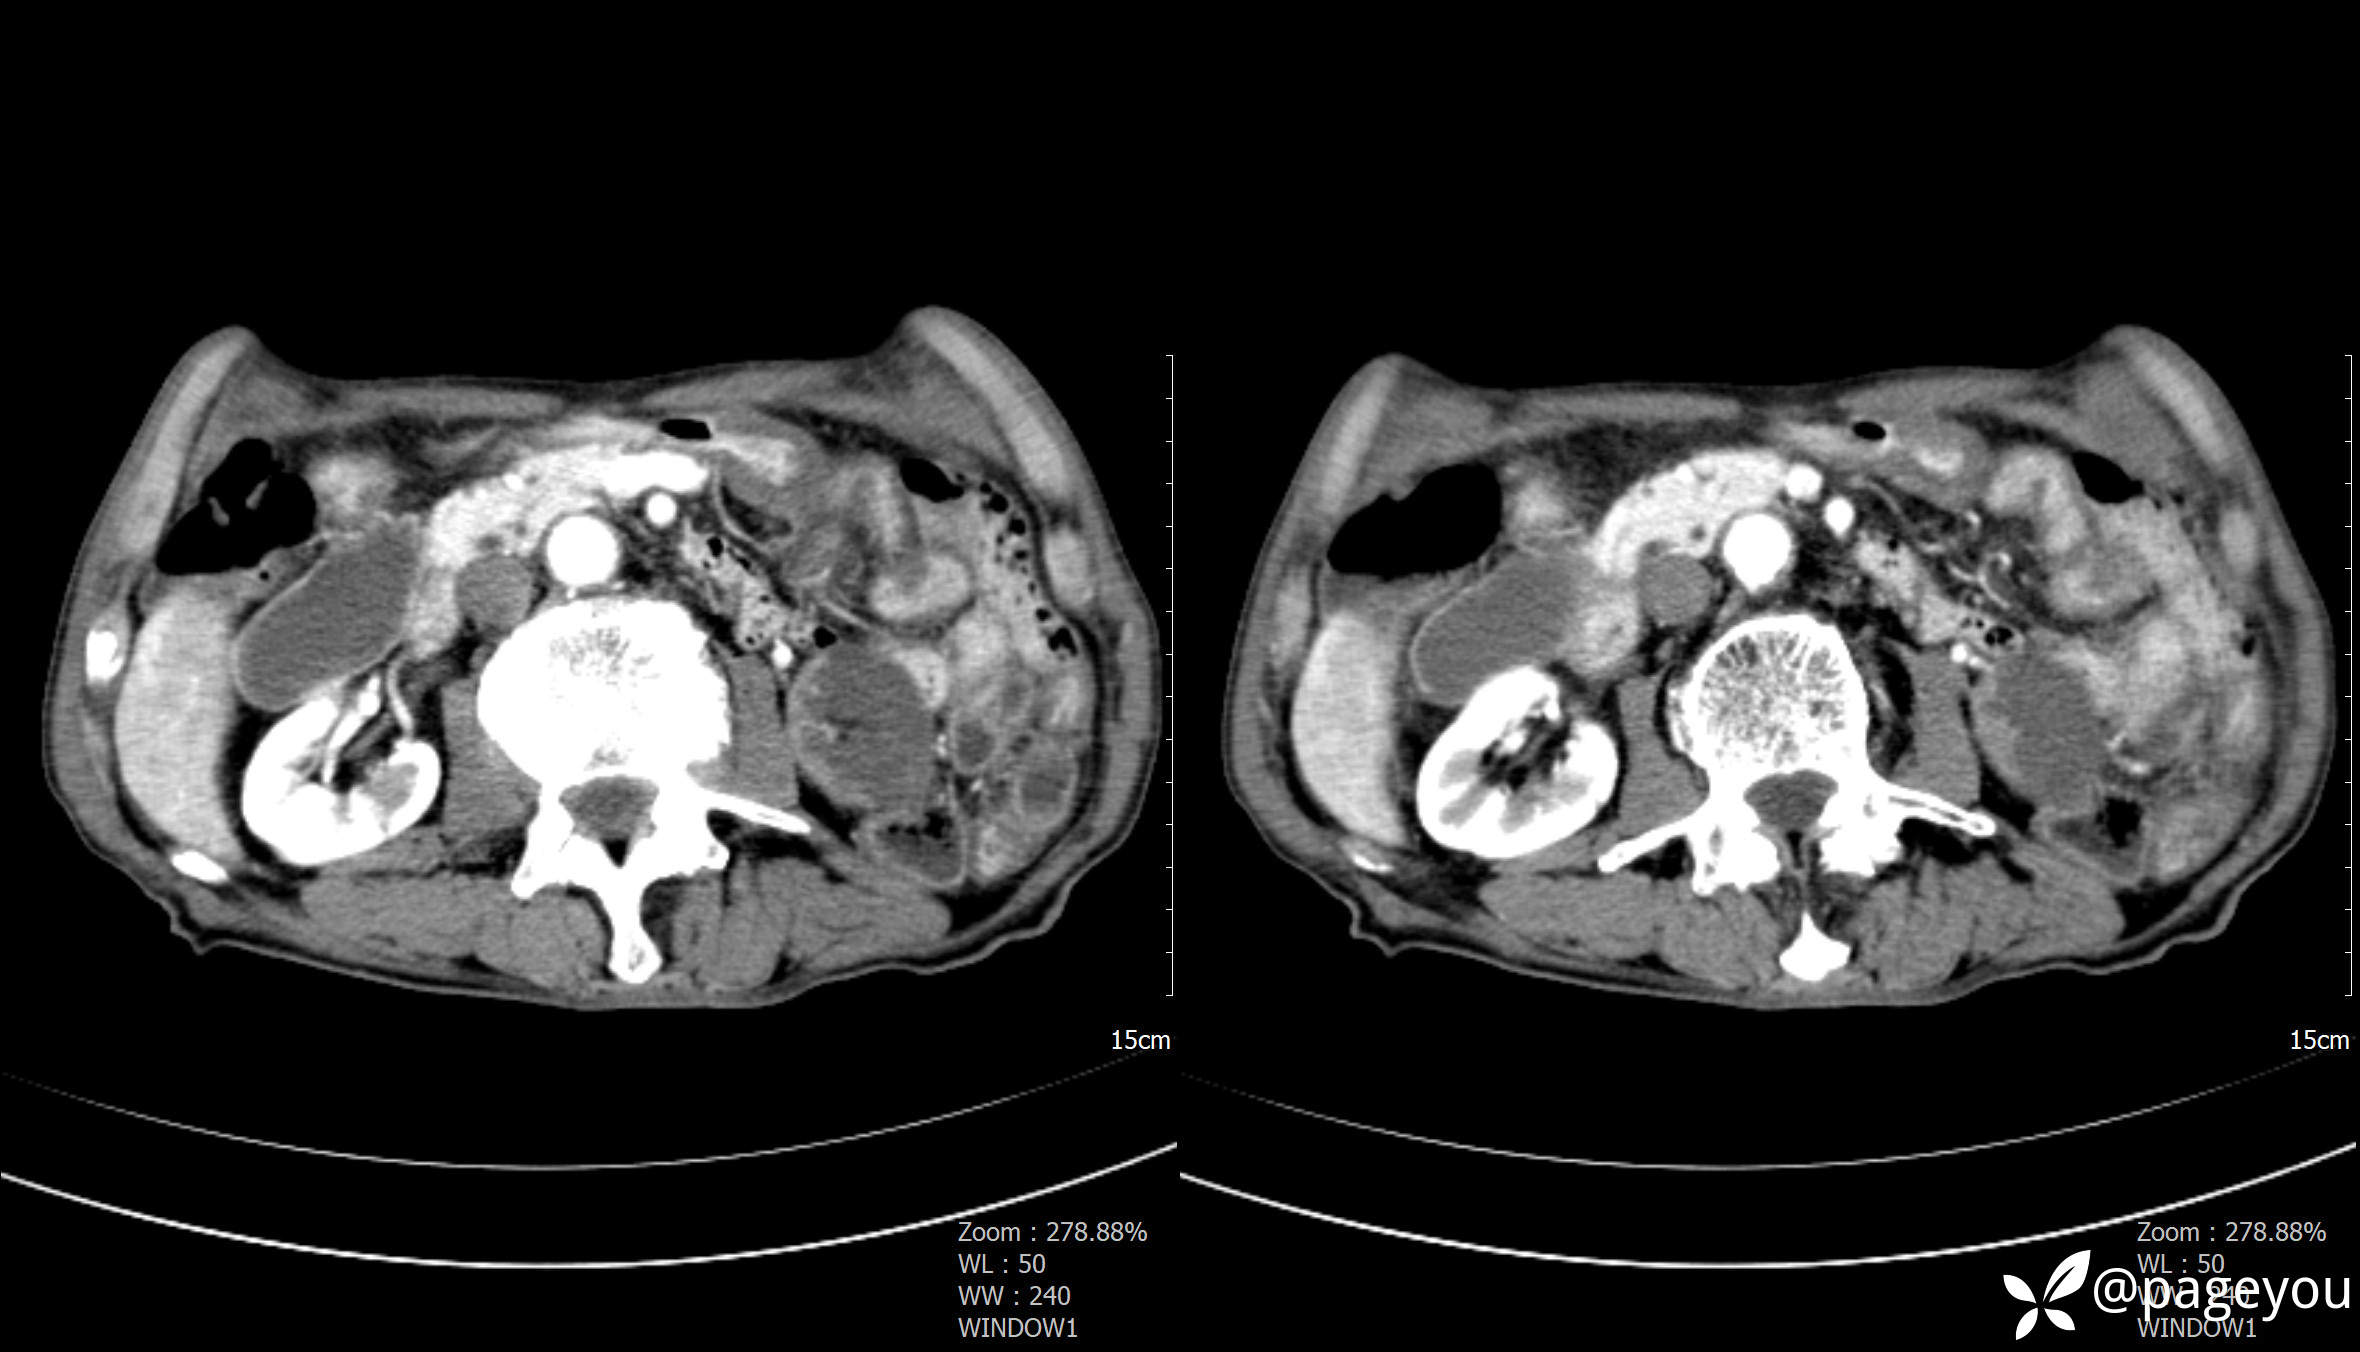

主动脉CTA: